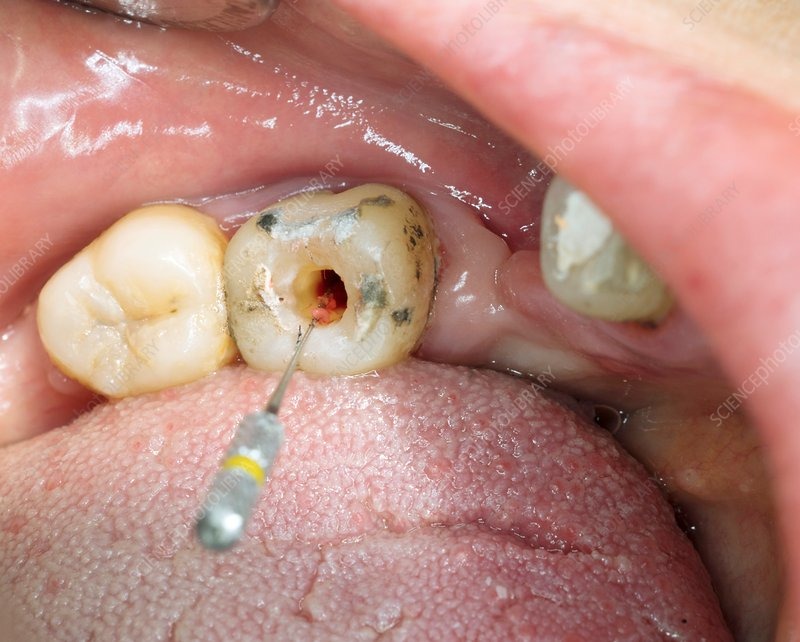

RCT, in a dental context, stands for Root Canal Treatment, also known as endodontic treatment. It's a procedure to repair and save a badly damaged or infected tooth, involving the removal of infected pulp, cleaning and disinfecting the canals, and sealing them to prevent future infection.